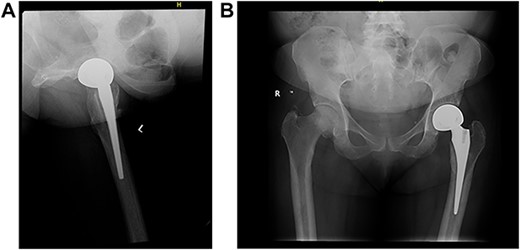

The patient was then referred to an outpatient physical therapy center to resume her physiotherapy. The patient achieved full weight bearing and excellent range of motion within 2 months postoperatively. Implants remained in good position showing no signs of loosening on x-rays (Fig. 4) on the ninth month visit, and she denied any pain with walking and had excellent range of motion at the time.

(A) Left (L) view of the implant in position; (B) Pelvic X-ray showing the implant in position.